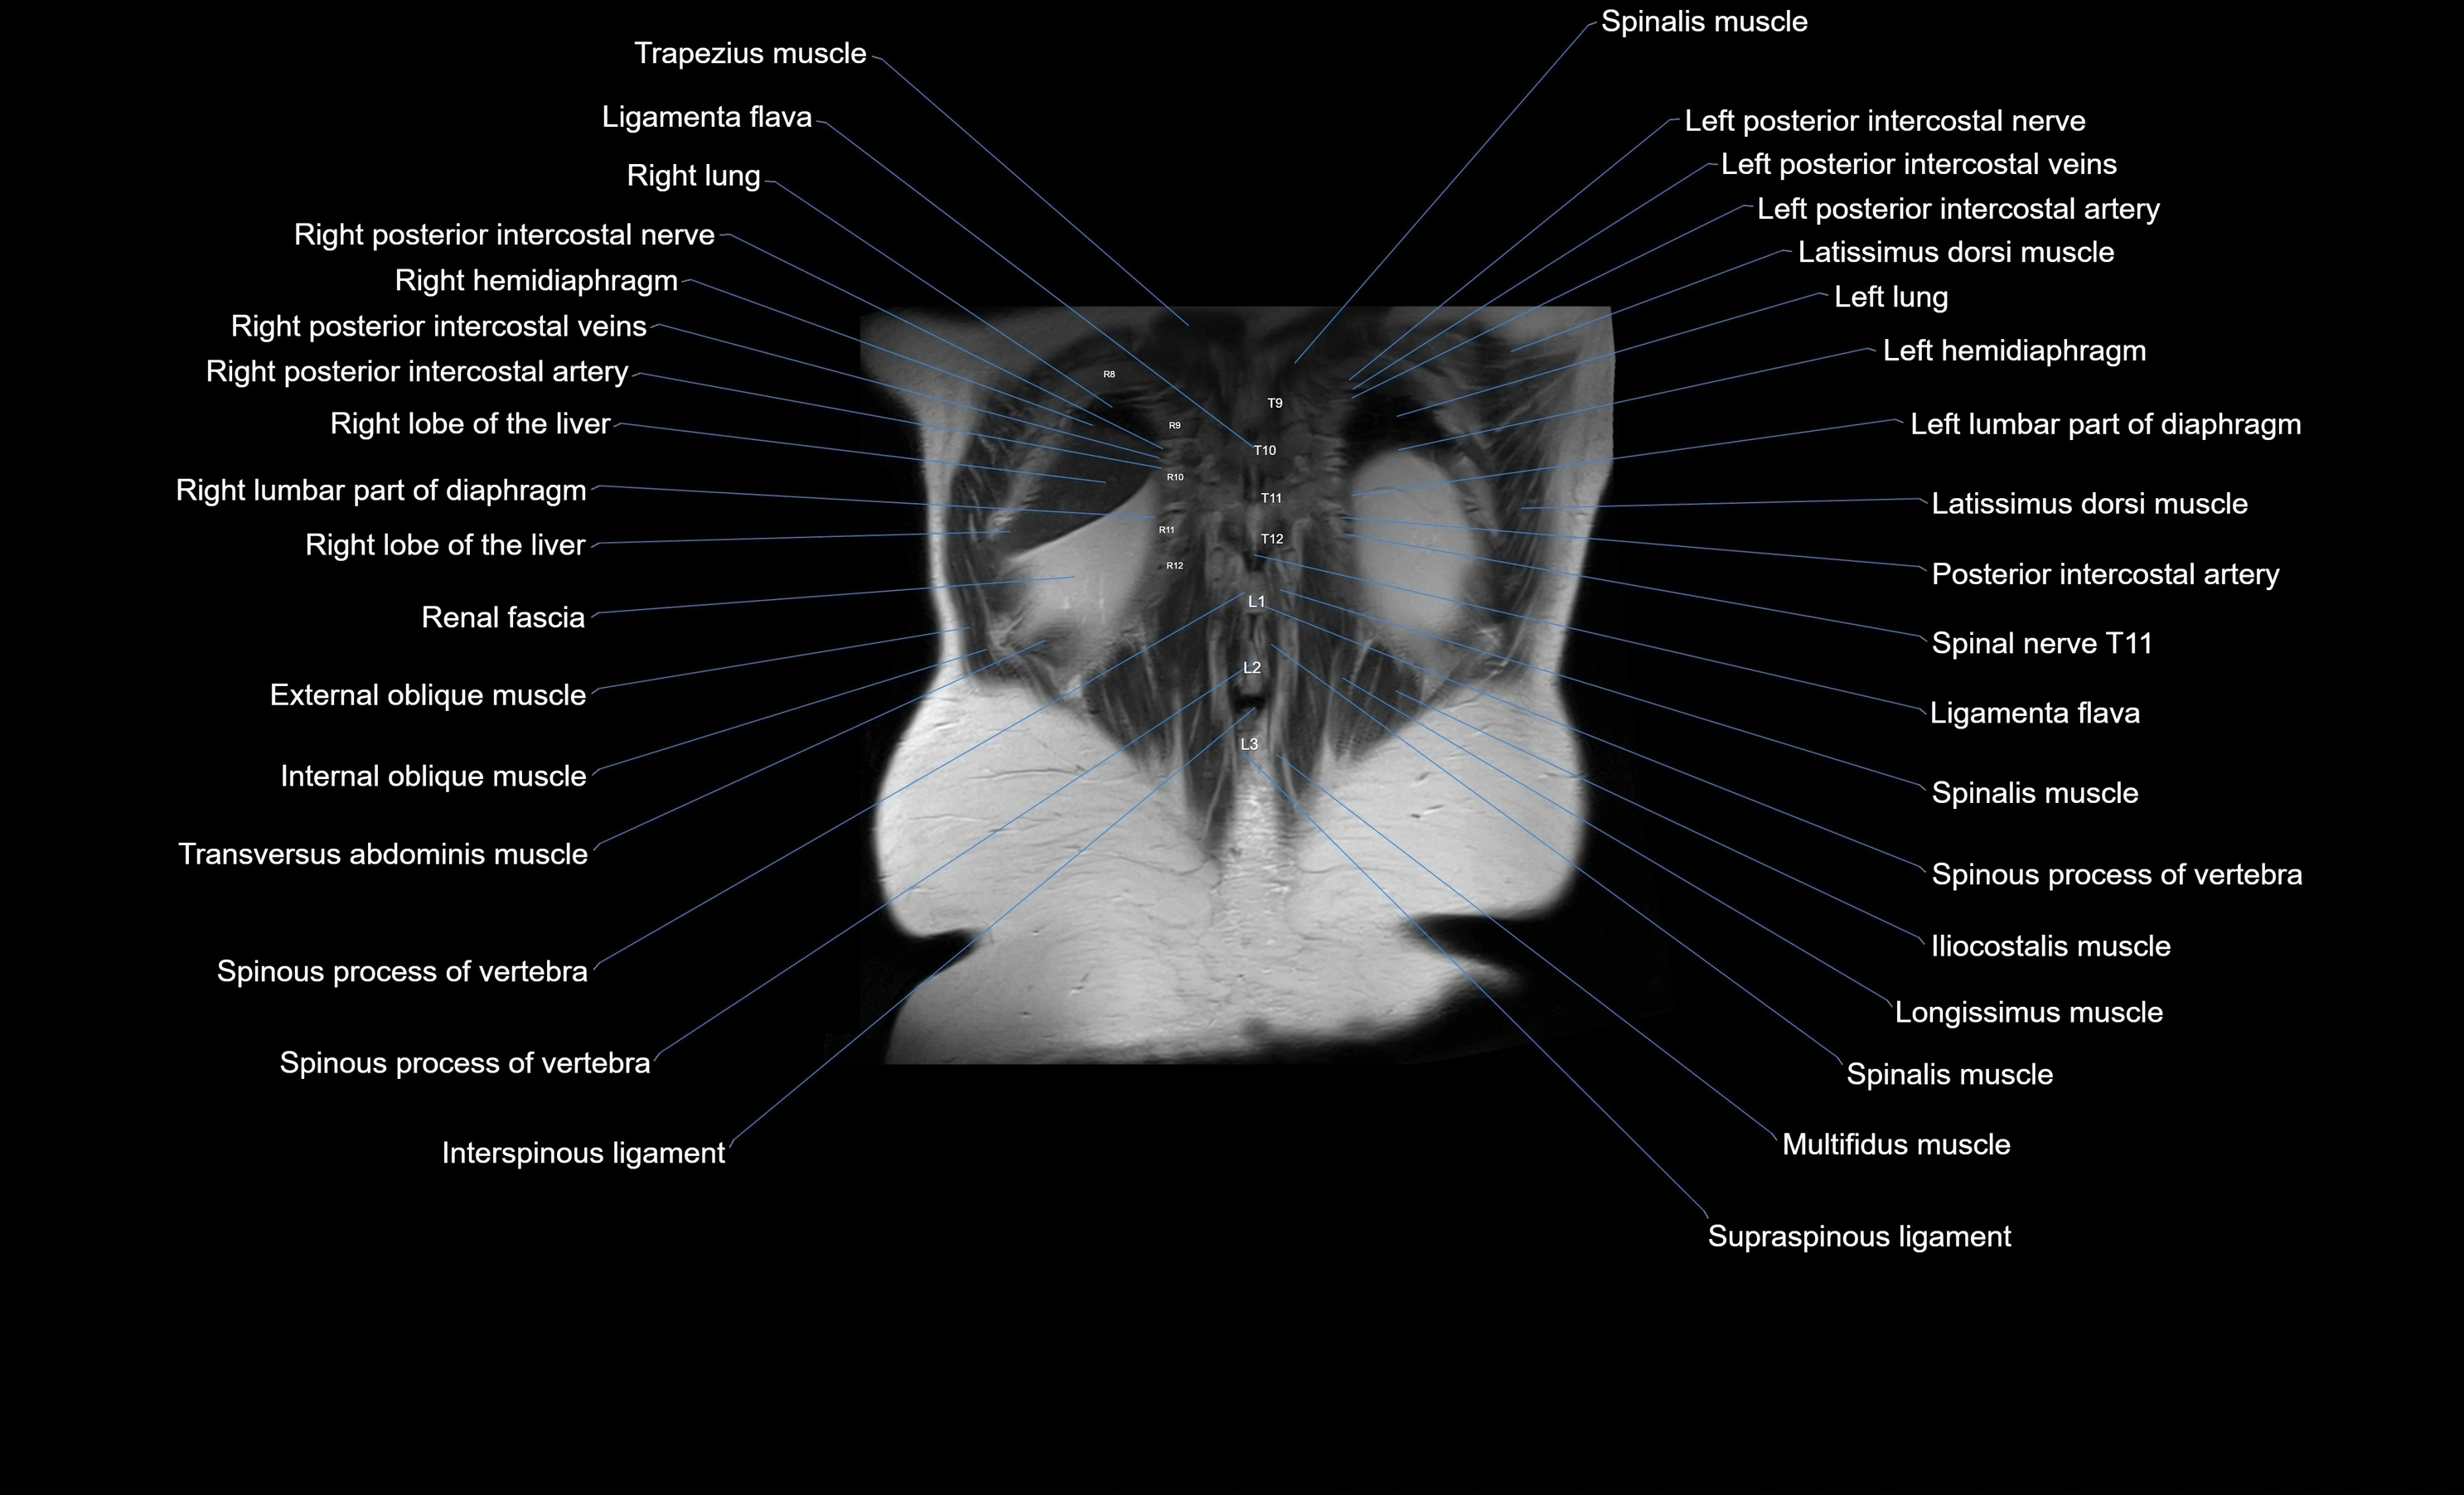

MRI images